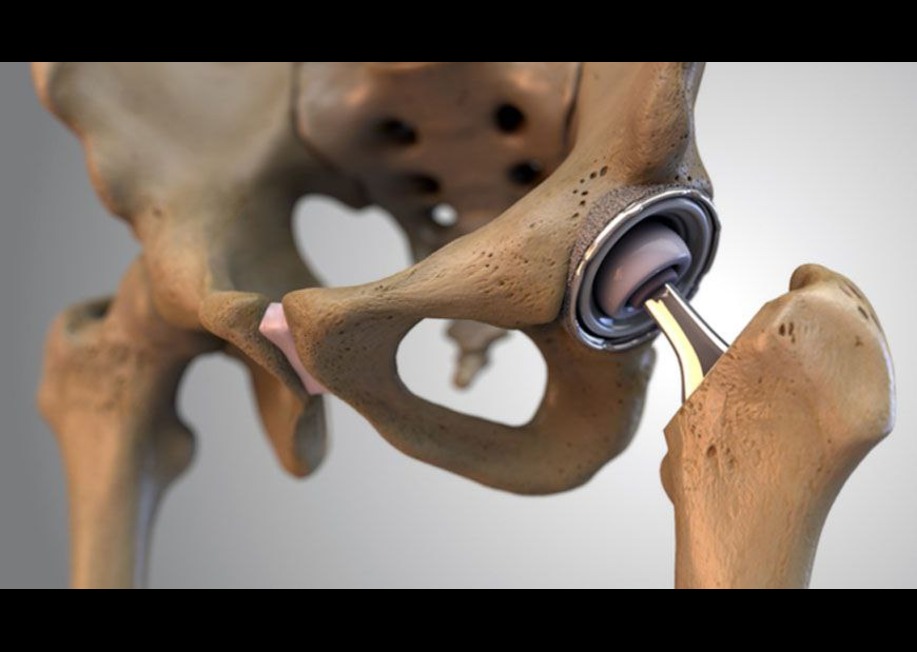

تعویض مفصل ران یکی از جراحیهای رایج ارتوپدی است که برای جایگزینی مفصل ران آسیبدیده با یک مفصل مصنوعی (پروتز) انجام میشود. این جراحی به طور معمول برای بیمارانی انجام میشود که از درد شدید و محدودیت حرکتی ناشی از آسیبهای مفصلی یا بیماریهای تخریبی مفصل رنج میبرند. مفصل مصنوعی معمولاً از موادی مانند فلز، سرامیک و پلاستیکهای بسیار مقاوم ساخته میشود. هدف اصلی از انجام این جراحی کاهش درد، بهبود دامنه حرکتی و بازگرداندن عملکرد طبیعی مفصل ران است. تعویض مفصل ران معمولاً به بیمارانی توصیه میشود که روشهای درمانی غیرجراحی مانند فیزیوتراپی، داروهای ضدالتهابی و تغییرات سبک زندگی نتوانستهاند درد و مشکلات حرکتی آنها را بهبود بخشند.

روش های فیکساسیون پروتز مفصل ران

روشهای فیکساسیون پروتزهای مفصل ران به طور عمده به دو دسته تقسیم میشوند: فیکساسیون با سیمان و فیکساسیون بدون سیمان. هر کدام از این روشها مزایا و معایب خاص خود را دارند و انتخاب آنها بستگی به شرایط بیمار و نوع جراحی دارد.

- فیکساسیون بدون سیمان:

در این روش، پروتز بدون استفاده از سیمان در استخوان قرار میگیرد. به جای سیمان، سطح پروتز طوری طراحی شده که استخوان بتواند به آن بچسبد و رشد کند (به این فرآیند “استخوانی شدن” گفته میشود). این روش به خصوص برای بیماران جوانتر که تراکم استخوانی خوبی دارند مناسب است. اگرچه فیکساسیون بدون سیمان زمان بیشتری برای دستیابی به استحکام نهایی نیاز دارد، اما در طولانیمدت معمولا نتایج بهتری دارد، زیرا نیاز به جراحی مجدد کمتر است.